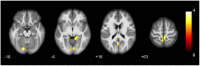

Results: HIV+ HoM showed significantly increased GMV in the bilateral parahippocampal gyrus and amygdala, and decreased GMV in the right inferior cerebellum, compared with the HIV- HoM. The brain regions with increased GMV were hyper-connected with the left superior cerebellum, right lingual gyrus, and left precuneus in the HIV+ HoM. Moreover, the ALFF values of the right fusiform gyrus, and left parahippocampal gyrus were increased in the HIV+ HoM. The regional homogeneity values of the right anterior cingulate and paracingulate gyri, and left superior cerebellum were decreased in the HIV+ HoM.

Conclusion: When the study population was restricted to HoM, HIV+ individuals exhibited structural alterations in the limbic system and cerebellum, and functional abnormalities in the limbic, cerebellum, and visual network. These findings complement the existing knowledge on the HIV-associated neurocognitive impairment from the previous neuroimaging studies by controlling for the potential confounding factor, sexual orientation. Future studies on brain alternations with the exclusion of related factors like sexual orientation are needed to understand the impact of HIV infection on neurocognitive function more accurately.